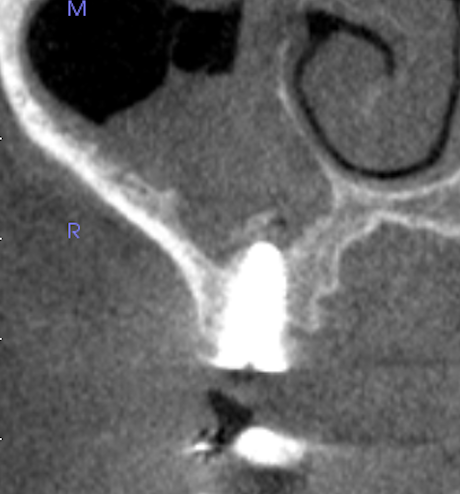

治療後

このケースでは上顎洞の手術をする際にリスクとなる、後上歯槽動脈の位置と隔壁や上顎洞の形態的にサイナスリフトが非常に困難な状況でした。合わせて、患者様の希望により可能な限り治療期間を短くしてほしいとのことも踏まえてソケットリフトによる抜歯即時インプラント埋入術を行いました。

この術式では診断や技術はもちろんのこと、リンキヴィシャス先生のゼロボーンロスコンセプトとストローマン社のインプラントが鍵となっております。

従来はインプラント体の先端部での固定を重要視しており、ソケットリフトにはある程度の骨長と先端部を覆うだけの骨移植が必要でした。その分、適応症が限られていました。

しかし、現在では側方骨での固定の有効性がわかり幅の広いワイドインプラントを使用することで必ずしもガイドライン上の骨長がなくてもソケットリフトが可能なケースが増えてきました。